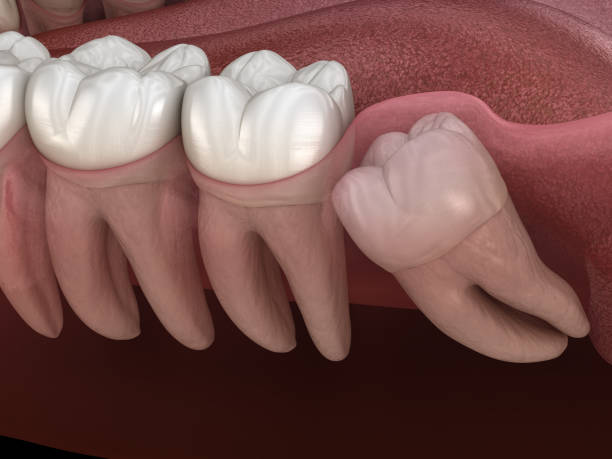

사랑니 발치를 앞두고 있거나 이미 발치한 분들이 가장 궁금해하는 것 중 하나가 바로 '뭘 먹어야 할까?' 그리고 '통증을 어떻게 줄일 수 있을까?' 하는 점일 텐데요.

오늘은 사랑니 발치 후 추천 식사 메뉴와 통증 줄이는 방법에 대해 자세히 알려드리겠습니다!